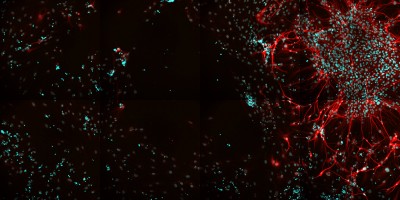

Although not as well-known as Alzheimer’s disease, frontotemporal dementia (FTD) is a serious health problem. It is the second most common cause of dementia after Alzheimer’s disease and the most common cause in those under age 65. It involves the loss of neurons in the frontal (behind the forehead) and temporal (over the ears) lobes of the brain. FTD is hard to diagnose, but it generally involves problems with changes in social behavior and conduct, loss of understanding of words, and difficulty in speaking. Unlike Alzheimer’s disease, FTD does not affect memory.